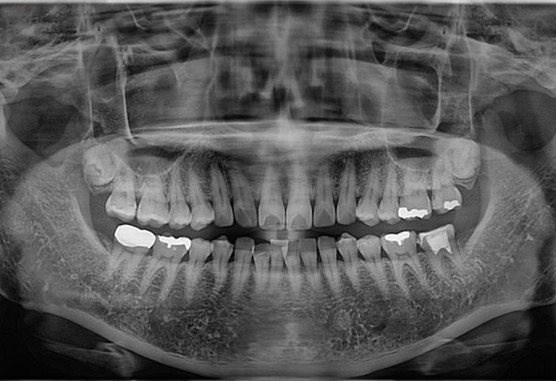

[2022. 07. 21 보철물 셋팅]

치아에 잘맞게 씌워진걸 볼 수 있습니다. 이상소견없어 보철물 마무리 후 치료 종결하였습니다.

일반적으로 치아에 금이가면 발치 후 임플란트를 하자는 치과가 많지만,

이번 케이스에서는 살릴려는 노력을 했음에도 불구하고 증상 호전이 되지않아 발치를 설명 하신듯합니다.

운이 좋게도 다른 치료방법을 이용해서 발치 하지않고 잘 마무리 된 치료 케이스입니다.